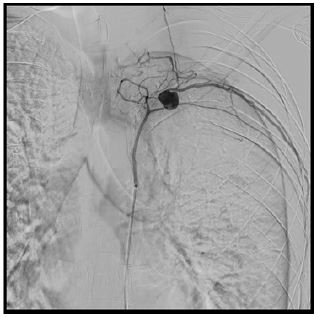

The patient underwent superselective arterial embolization of the involved intercostal artery (Figure 1). The procedure was successfully performed using microcoils (3 and 4 mm), obtaining immediate stop of bleeding (Figure 2). A left chest tube was placed and 1200 mL of blood were evacuated. The patient then underwent videothoracoscopic debridement to evacuate clots and some retained blood.

Figure 2: Successful superselective arterial embolization.